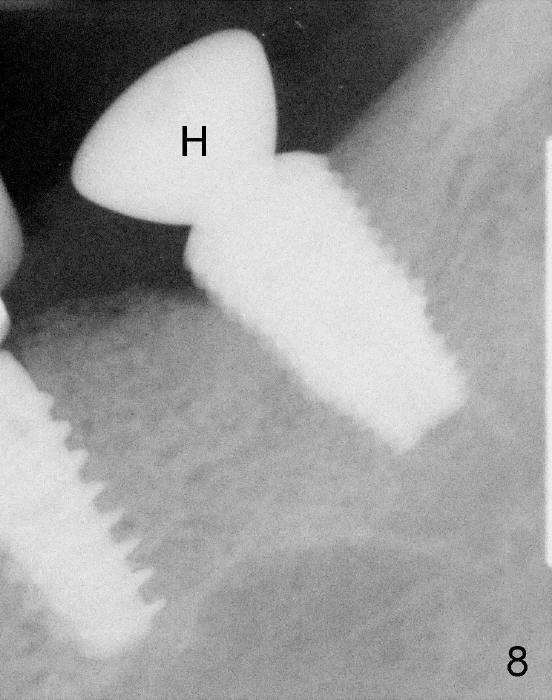

The patient returns for follow up 5 months postop (Fig.8) and abutment insertion 7 months postop (Fig.9,10).